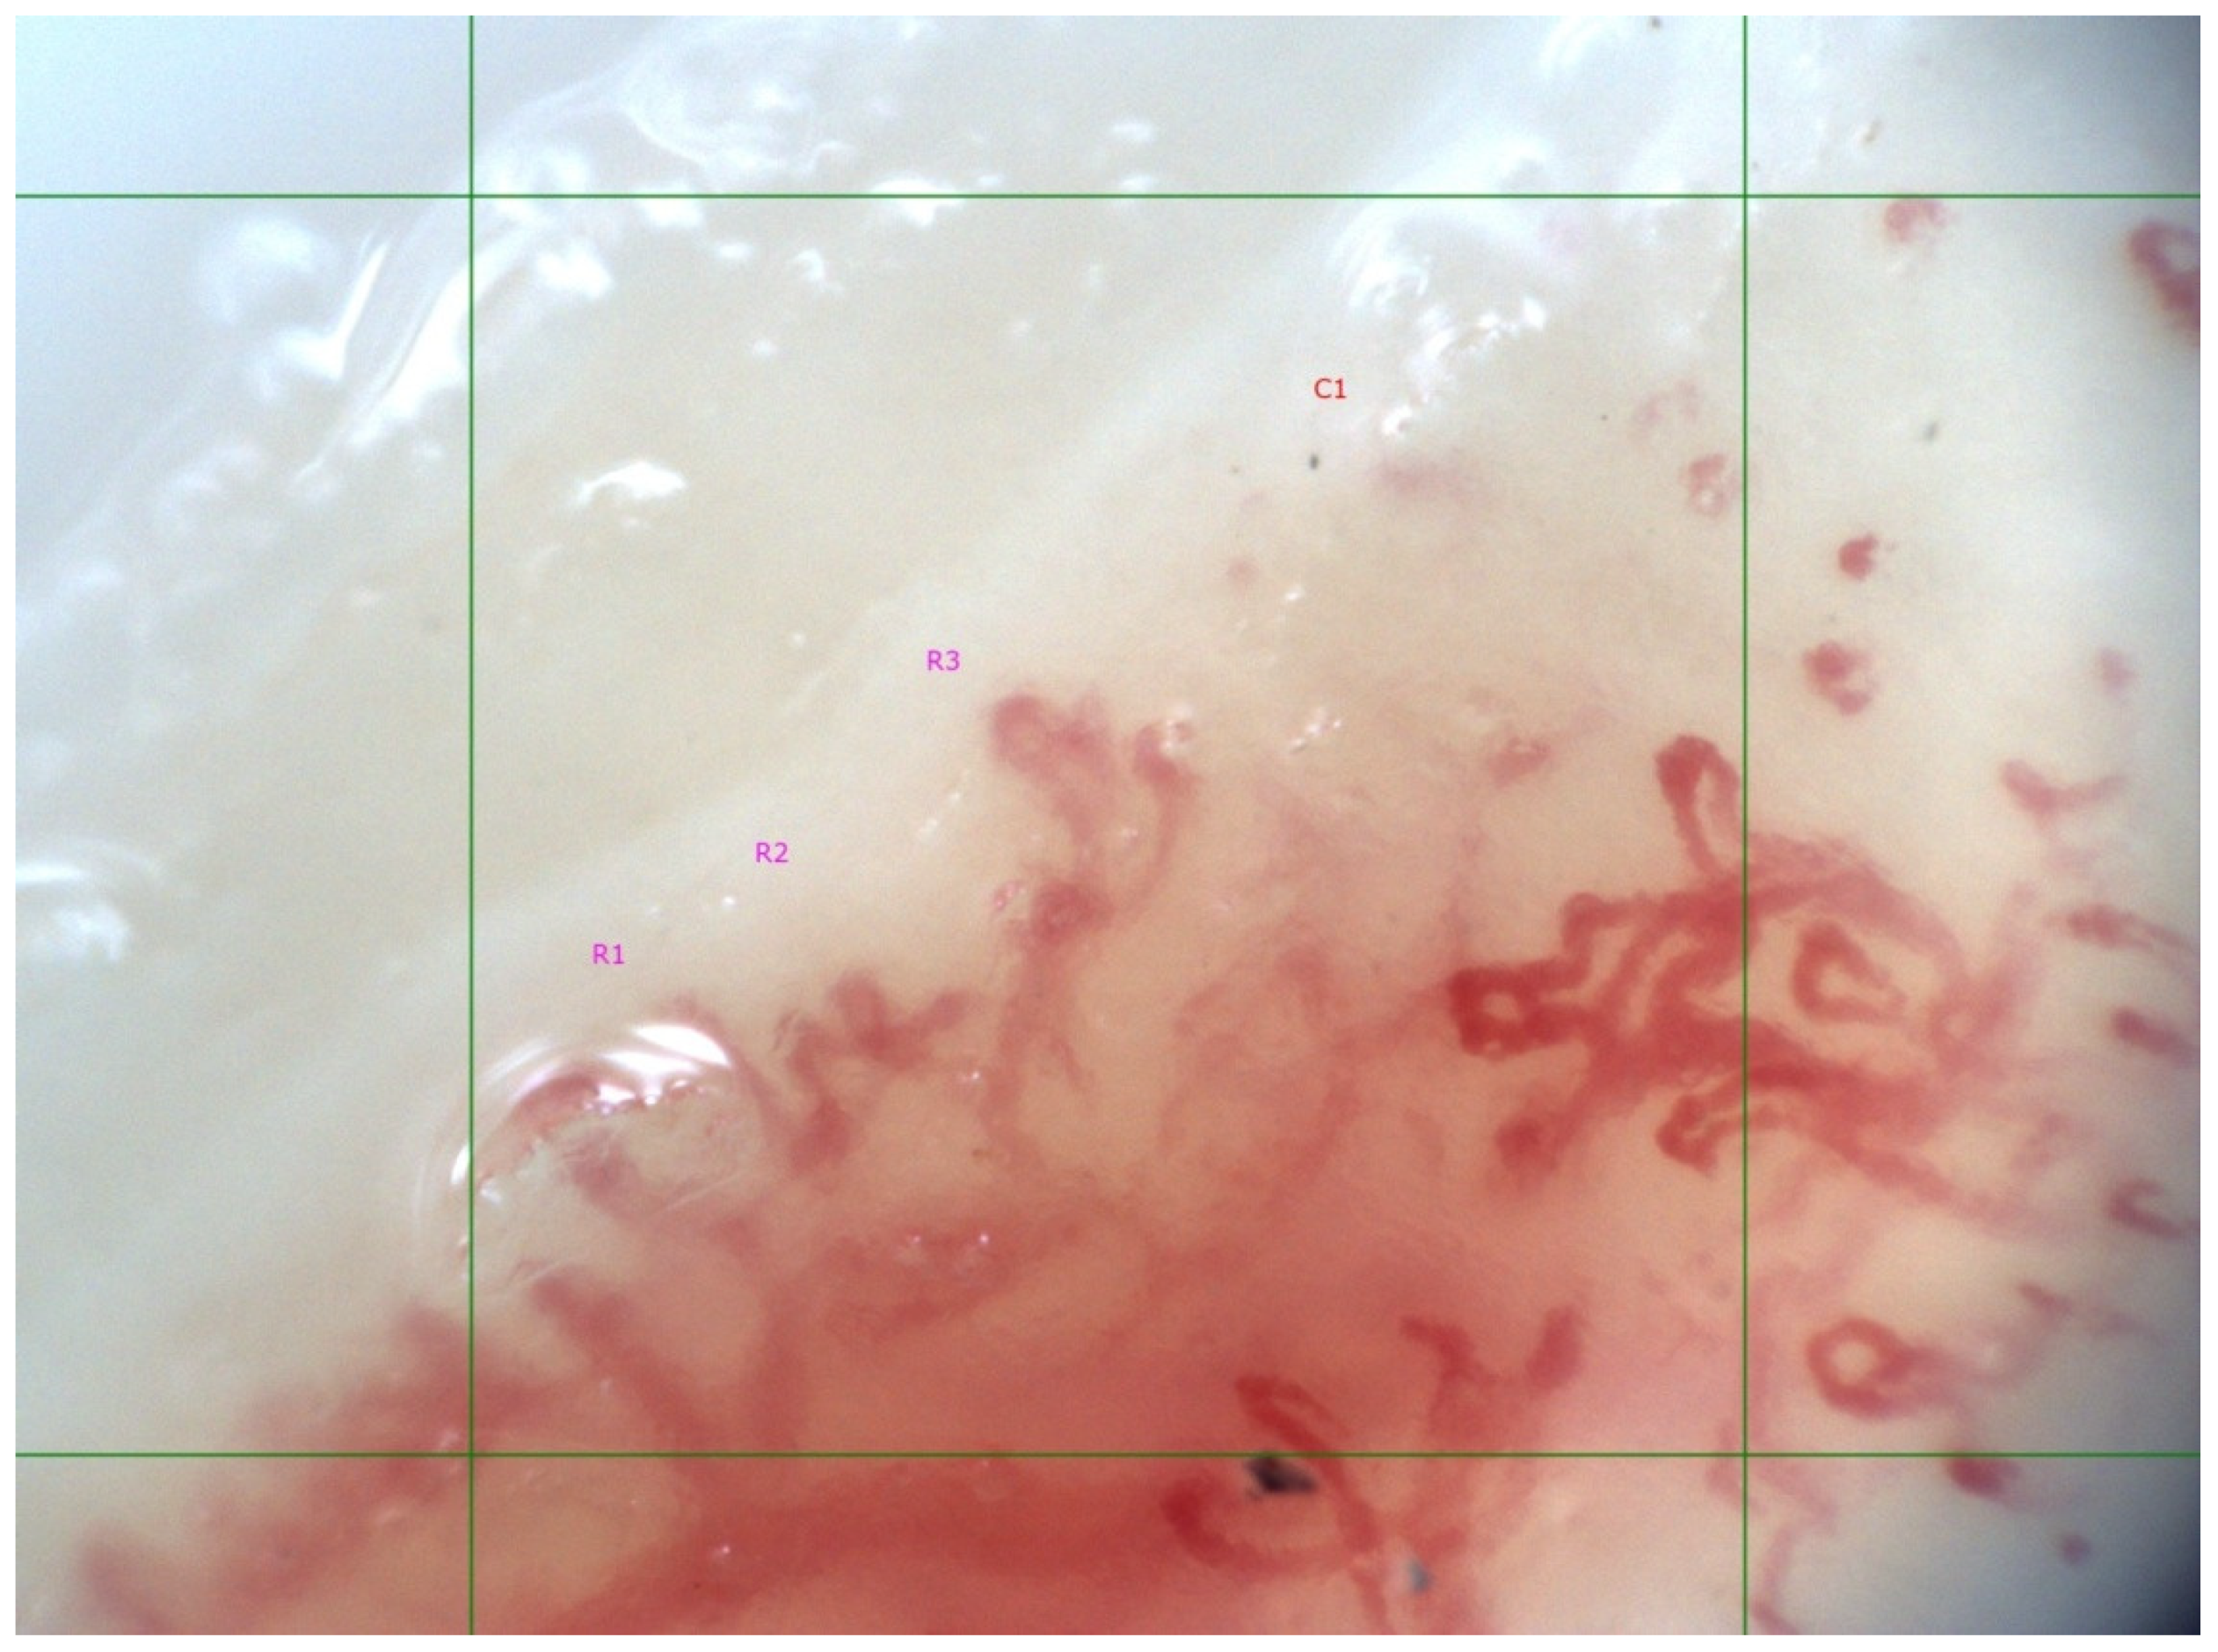

- Lambova, S.N.; Muller-Ladner, U. Inhomogeneity of capillaroscopic findings in systemic sclerosis. Int. J. Rheum. Dis. 2019, 23, 207–215. [Google Scholar] [CrossRef] [PubMed]